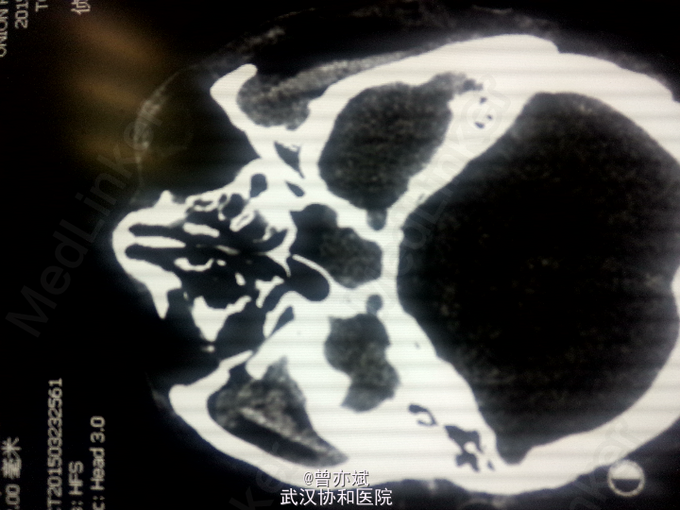

因“车祸伤1日余”入院。 现病史:患者1日前因车祸伤及头部,伤后神志昏迷,呼之不应,急送至当地医院,行CT检查示左额硬膜外血肿,并行清创缝合术,今为求进一步治疗来我院就诊,急诊以“脑外伤”收入我科。 病程中,患者神志昏迷,查体不合作。

查体:T 36.9℃,P 70次/分,R 20次/分,BP 128/82mmHg,查体不合作,神志浅昏迷,营养发育良好,皮肤及淋巴结未及明显异常,头颅大小正常,无畸形,头发分布正常,左额部软组织损伤,心肺腹未及明显异常。双下肢无水肿,生理反射存在,病理反射未引出。 专科查体:神志浅昏迷,GCS评分3+3+4分,左侧瞳孔直径6mm,对光反射消失,右侧瞳孔直径4mm,对光反射存在,四肢肌力2级,生理反射存在,病例反射未引出。 辅助检查:外院及我院急诊CT示左侧额部硬膜外血肿。急诊CT:1、左侧额部硬膜外血肿,厚度为23mm;2、少量蛛网膜下腔出血;左侧额骨线性骨折累及左侧眶顶、内侧壁及眶突,左侧眼眶内侧壁局部凹陷,考虑为外上性改变,左侧筛窦积液、积血、蝶窦积液。